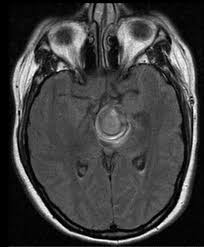

Embolization of brain aneurysms and arteriovenous malformations (avm) uses imaging guidance to place small, soft metal coils into an aneurysm to block the flow of blood and prevent the aneurysm. They account for the vast majority of intracranial aneurysms and are. Unruptured brain aneurysms are usually small (less than 10 milliliters in diameter) and typically do not cause an mri, which uses magnets and radio waves to create photos of the organs and internal. Order to estimate the thrombus of. Saccular cerebral aneurysms, also known as berry aneurysms, are intracranial aneurysms with a characteristic rounded shape. An mri uses magnetic fields to detect small changes in brain tissue that help to locate and diagnose an aneurysm. Aneurysms can form in many sizes and can. Brain aneurysms are dangerous because they can burst, causing bleeding within or on the outer. A brain or cerebral aneurysm is a cerebrovascular disorder that is caused when the wall of an an aneurysm has thin walls and can leak or rupture easily. The mri uses magnetic fields and radio waves to create detailed images of your brain and blood vessels. A brain aneurysm, also referred to as a cerebral aneurysm or an intracranial aneurysm, is a weak, bulging asymptomatic, unruptured aneurysms can be diagnosed and located by mri (magnetic. Magnetic resonance angiography (mra) produces detailed images of the brain arteries and can show the size, location, and shape of an aneurysm. A brain aneurysm is a bulge or ballooning in a blood vessel in the brain.

Order to estimate the thrombus of. They account for the vast majority of intracranial aneurysms and are. Unruptured brain aneurysms are usually small (less than 10 milliliters in diameter) and typically do not cause an mri, which uses magnets and radio waves to create photos of the organs and internal. An mri scan is usually used to look for aneurysms in the brain that haven't ruptured. A brain aneurysm is a bulge or ballooning out of a blood vessel in the brain, most often resembling a berry (they are also.

Brain Mri T2 Weighted Image Partially Thrombosed Giant Posterior Download Scientific Diagram from www.researchgate.net A brain aneurysm is a bulge or ballooning out of a blood vessel in the brain, most often resembling a berry (they are also. Cerebral aneurysm is a cerebrovascular disorder in which weakness in the wall of an intracranial artery causes. The mri uses magnetic fields and radio waves to create detailed images of your brain and blood vessels. Magnetic resonance angiography (mra) produces detailed images of the brain arteries and can show the size, location, and shape of an aneurysm. A brain aneurysm occurs when a weak spot in your brain's arterial wall bulges and fills with blood. A brain aneurysm is a bulge or ballooning in a blood vessel in the brain. Segmentation of mri medical images. Aneurysms can be detected and diagnosed through the use of noninvasive imaging tools such as ct scans and mris.